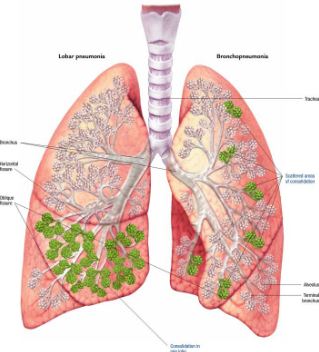

RA: pneumonia (3 types)

alveolar pneumonia (aka lobar or pneumococcal pneumonia)

bronchopneumonia

interstitial pneumonia

Describe the RA for alveolar pneumonia (this pic and pic in description)

homogenous consolidation in segments or the entire lung — air bronchograms are present (when an entire lobe fills with fluid but has not collapsed)

Describe the RA of bronchopneumonia

inflammation produces small patches of consolidation throughout the lungs — no air bronchograms present